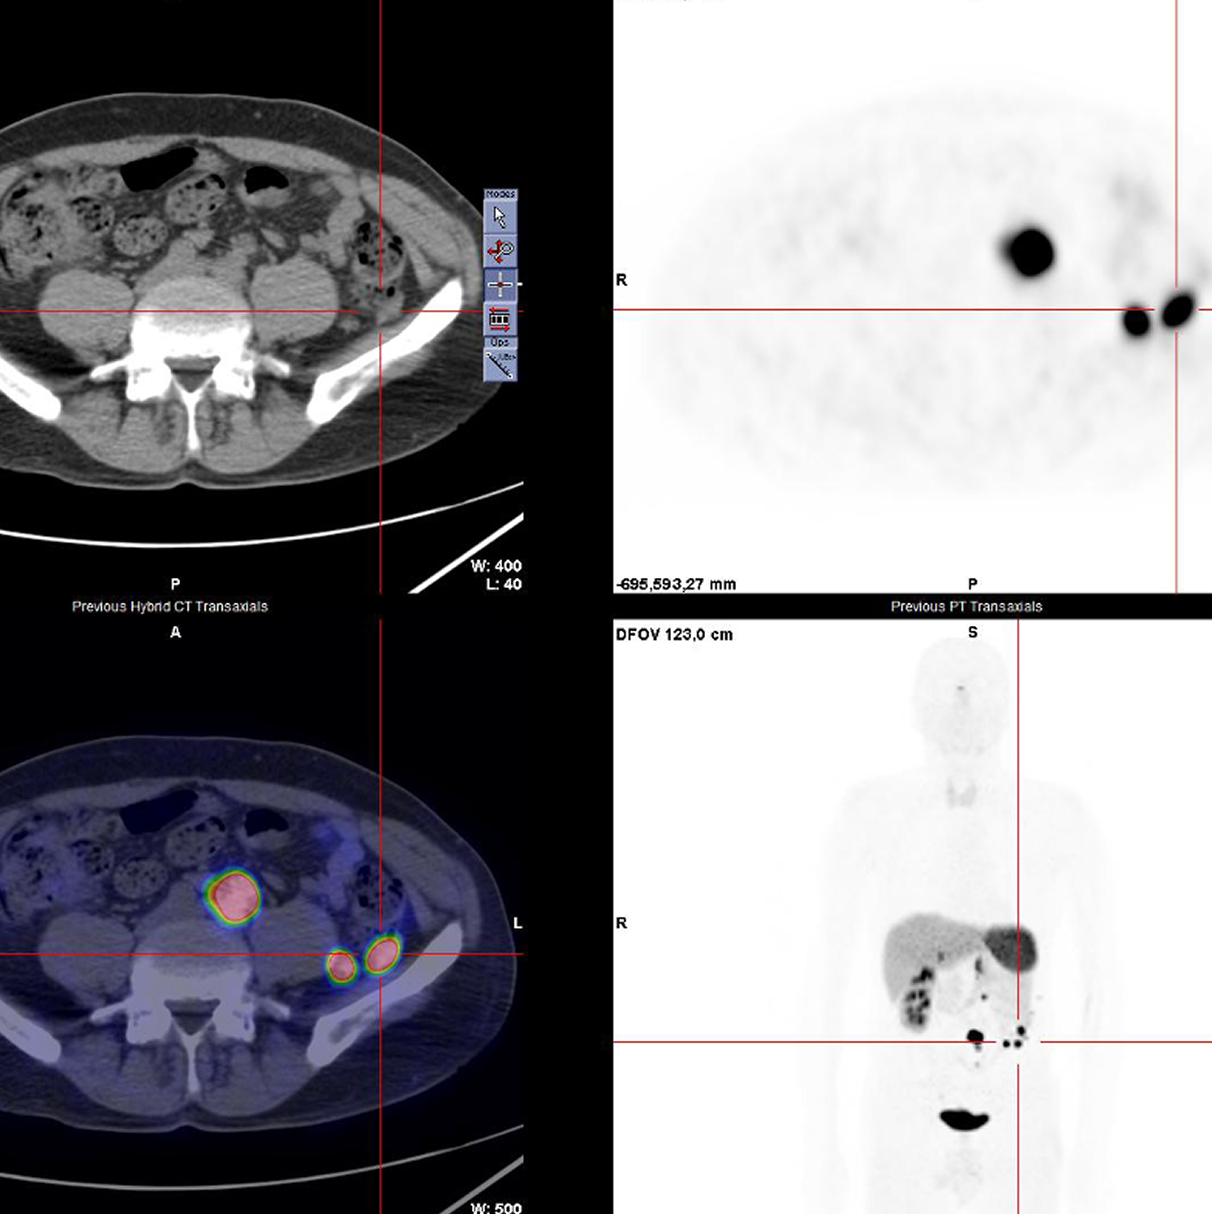

Casi clinici

Scopri come le tecnologie di imaging più innovative di GE HealthCare hanno giocato un ruolo chiave nella diagnosi di condizioni cardiache complesse.